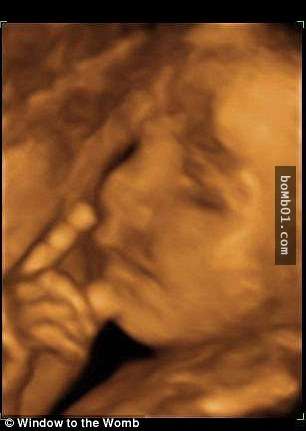

▼左邊這個寶寶看起來正在大喊,右邊這個寶寶則在思考人生。